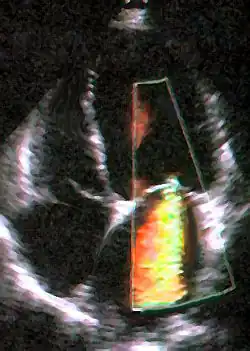

Echocardiogram

|

| Severe MR | Legend |

| 1 Left atrium (LA) – 2 MR Jet, LV Left ventricle – RV Right ventricle – RA Right atrium | |

An echocardiogram is commonly used to confirm the diagnosis of MR.[16] Color doppler flow on the transthoracic echocardiogram (TTE) will reveal a jet of blood flowing from the left ventricle into the left atrium during ventricular systole. Also, it may detect a dilated left atrium and ventricle and decreased left ventricular function.[6] A transesophageal echocardiogram can give clearer images if needed as the back of the heart can also be viewed.[17]